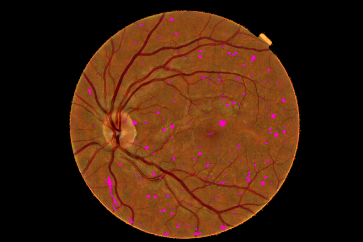

Refer to caption

Figure 4: Pixel probability maps obtained from the final CNN for a different number of epochs. In initial epochs, the probability map include low probabilities of MA (depicted as green spots), in the subsequent epochs, the medium and high probabilities are in blue and purple respectively.